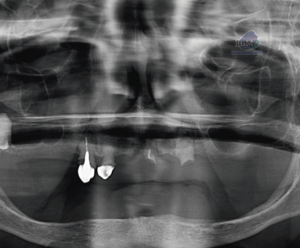

Radiografia Panorámica

En la radiografía panorámica se evidencian múltiples restauraciones coronarias, así como tratamiento de conductos en la pieza 47. En la pieza 23 se aprecia una disminución de la densidad radicular en la región cervical.